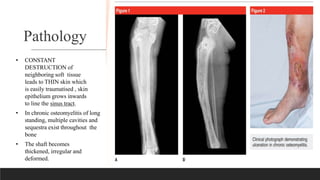

Pathology

• CONSTANT

DESTRUCTION of

neighboring soft tissue

leads to THIN skin which

is easily traumatised , skin

epithelium grows inwards

to line the sinus tract.

• In chronic osteomyelitis of long

standing, multiple cavities and

sequestra exist throughout the

bone

• The shaft becomes

thickened, irregular and

deformed.